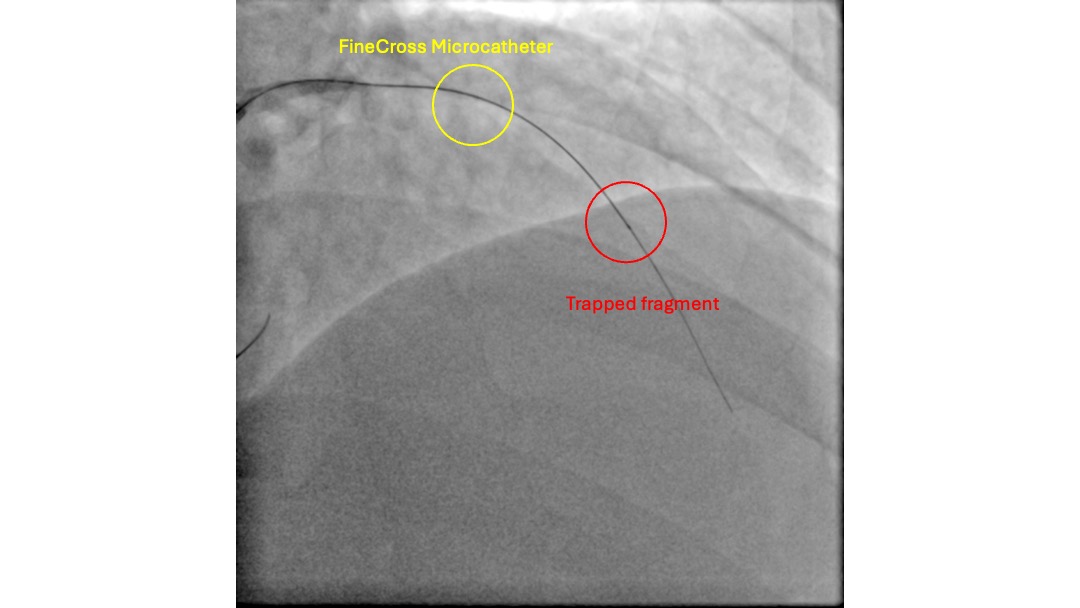

With the support of a FineCross micro-catheter (MC), the proximal CTO cap was punctured with a Gaia First wire. The wire traversed the CTO body through the intra-plaque space without much difficulty, reaching the distal lumen, which was confirmed by contralateral injection. However, the MC could not be delivered to the distal lumen over the Gaia First wire. The CTO lesion was pre-dilated with a 1.0 mm balloon, but it burst during the fourth inflation, and the MC still failed to advance. Subsequently, a trapped foreign body was noted on the distal aspect of the wire that prevented the advancement of the MC. This was initially thought to be a fragment fractured from the 1.0 mm balloon. The intervention was continued over the Gaia First wire to facilitate the removal of the fragment. The lesion was pre-dilated with a 2.5 mm non-compliant (NC) balloon and a 3.5 mm cutting balloon. Two 3.5 mm drug-coated balloons (DCBs) were then used to treat the lesion. With adequate luminal gain, an extension catheter was advanced into the LAD, and the fragment was retrieved inside it. A 1.5 mm balloon was then deployed to trap the fragment inside the extension catheter. The wire, extension catheter, and inflated 1.5 mm balloon were then removed simultaneously from the LAD. Inspection of the wire revealed that the fragment was, in fact, an unraveled coronary wire rather than a fractured balloon.